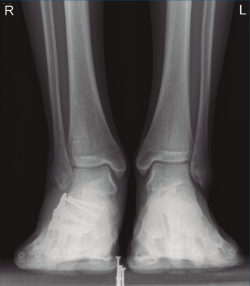

A los 9 meses únicamente presentó dolor ocasional al nivel de la articulación subastragalina y molestias en la planta del pie al deambular descalzo, por lo que se pauta plantilla amortiguadora, con la que mejora notablemente la sintomatología. Presentó una puntuación de 83 sobre 100 en la escala de la American Orthopaedic Foot and Ankle Society (AOFAS), ligeramente superior a la media descrita en estudios previos(2,3). Radiográficamente se evidenció una anatomía restablecida del calcáneo y de la sindesmosis, así como una altura adecuada de ambos tobillos (Figuras 12 y 13). Dada la buena evolución, se decidió continuar con el seguimiento anual del paciente sin realizar la extracción del material de osteosíntesis, para valorar la necesidad de una futura artrodesis subastragalina.

Figura 13. Radiografía anteroposterior de ambos tobillos a los 9 meses de la cirugía.